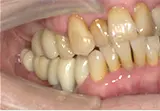

| 年齢/性別 | 60代女性 |

| 主訴 | 前歯が前に出てきた |

| 治療内容 | 全体的に歯周病やむし歯、根の治療(ヘミセクション)を実施。右上の歯にはサイナスリフト術を行い、骨の回復を待った後、半年後に2本のインプラントを埋入しました。 |

| 治療期間 | 9か月 |

| 費用 | 1,298,000円税込 |

| リスク・副作用 | 炎症反応によって術後に腫れや副鼻腔炎が生じることがあります。その程度は、手術の範囲や方法によって異なりますが、多くの場合、時間の経過とともに徐々に治まります。

ごく稀に、下顎奥歯の外科手術後に、唇や顎に痺れを感じることがあります。 |